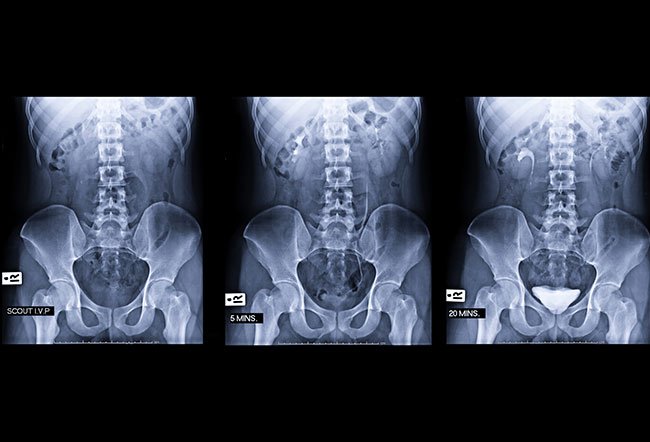

A kidney, ureter, and bladder (KUB) X-ray is a diagnostic test that is used for detecting kidney stones and diagnosing multiple disorders of the urinary tract. This diagnostic examination is usually done by injecting contrast media in your veins.

A KUB X-ray evaluates the urinary tract before other procedures are performed. Basic information regarding the kidney size and shape and position of the ureters and bladder is obtained with a KUB X-ray. The presence of calcification in the kidneys or ureters may point to stones in the urinary system.

- The patient is positioned on the table, and still X-ray images are taken. A contrast material is then injected, usually in a vein in the patient's arm, followed by additional still images.

- Because the contrast material is processed by the kidneys, a series of images are taken to determine the actual size of the kidneys and to capture the urinary tract in action as it begins to empty.